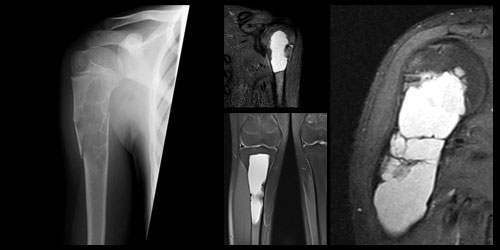

Osteosarkom

Kemiğin en sık 2. kanseridir. Yıllık insidansı 4-6: 1 milyondur. Çoğu primer dediğimiz kendiliğinden ortaya çıkarken nadiren sekonder dediğimiz Paget hastalığı ya da radyasyon zemininde gelişebilir.